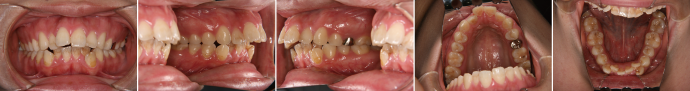

| 主訴 | 前歯が出ている |

| 年齢・性別 | 35歳 / 女性 |

| 治療方針 | 叢生も前歯の突出も大きいケース。小臼歯抜歯だけでは改善できないため、大臼歯の抜歯も行なった。 |

| 抜歯部位 | 上下顎左右小臼歯、左上第1大臼歯(計5本) |

| 使用装置 | マルチブラケット装置 |

| 治療期間 | 36か月 |

| リテーナー | 上顎インビジブル、フィックス、下顎インビジブル |

| 費用 | 885,000円(税別) |